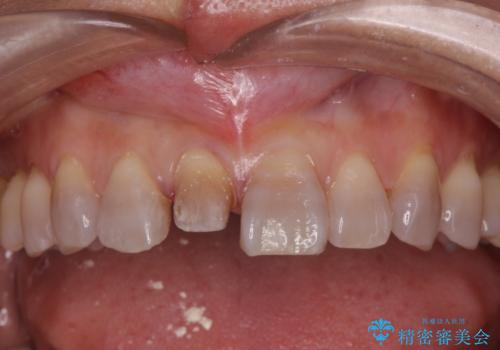

転んで前歯が折れた 色合いの難しい歯のセラミック修復

- 転倒し前歯を地面に強打して折れたとのことで来院。

幸い神経は生きており、セラミックでかぶせることになりました。

テトラサイクリン歯といって縞模様の強い歯の色調再現を行いました。

まず保険治療でコンポジットレジン修復を行い、神経の状態を確認した後、クラウンによる修復を行いました。